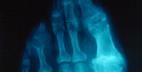

سبق وأشرنا الى أن مرض النقرس أو "داء الملوك" هو نوع من أنواع إلتهابات المفاصل، ويحدث بسبب ترسب حمض البوليك فى أنسجة المفاصل وما يحيط بها من غضاريف وعظام وعضلات. بالنسبة الى الأعراض فهي عادةً ما تكون مفاجئة، فتبدأ على الشكل التالي، آلام حادة بالمفصل مع تورم وإحمرار حوله مع إحتمال حصول إرتفاع في درجة الحرارة. لكن من المهم أن نلفت الى أن هذه الأعراض لا تلبث أن تختفي خلال إسبوع أو أكثر لتعاود الظهور مرة ثانية على فترات تمتد لعدة أسابيع أو أشهر أو حتى سنوات. كما أنها غالباً ما تظهر في فترات المساء. أما التشخيص فيعتمد على ملاحظة الأعراض ومن ثم الخضوع لتحليل مخبري لمعرفة نسبة زيادة نسبة حمض البوليك في الدم، ولو أن إرتفاع معدل حمض البوليك في الدم لا يعني دائماً الإصابة بمرض النقرس. ويتم التشخيص أيضاً عن طريق غرس إبرة في المفصل المصاب للحصول على عينة من سائل المفصل لفحصها مجهرياً. وقد يطلب الطبيب من مرضه صور أشعة وفحصاً للبول.